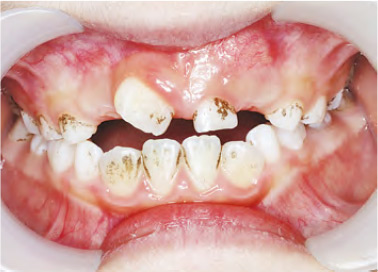

【明報專訊】家長經常因為擔心孩子牙齒上的黑斑而求醫,有些家長擔心這些污漬可能是蛀牙;有些則擔心會影響孩子外觀,尤其是在學校面試等重要活動之前出現斑點。

當不溶性鐵鹽沉積在牙齒上時,就會產生黑色牙漬。這是製造硫化氫的細菌與口水或牙肉中鐵質產生化學作用所導致。蛀牙通常會出現在咀嚼面、牙罅或難以觸及部位;而黑色牙漬則不同,它會沿着牙齒下半部形成黑色小點或線條。這種牙漬確切成因仍有爭議,有些人認為可能與細菌、飲食和牙齒護理等各種因素有關。

如果孩子有黑色牙漬,家長先放心,研究顯示,有這種牙漬的兒童不太會有蛀牙的問題。因為這些細菌佔據在兒童的口腔微生物群內,令引致蛀牙的細菌較少。儘管牙漬看起來並不美觀,但它本身不會對牙齒造成損害。若家長不喜歡有牙漬外觀,只要找牙醫作簡單洗牙,就可以輕鬆解決問題。雖然黑色牙漬過了不久很大可能會在牙面重現,但定期帶小朋友去清除牙漬相較為小朋友補牙、杜牙根容易得多。